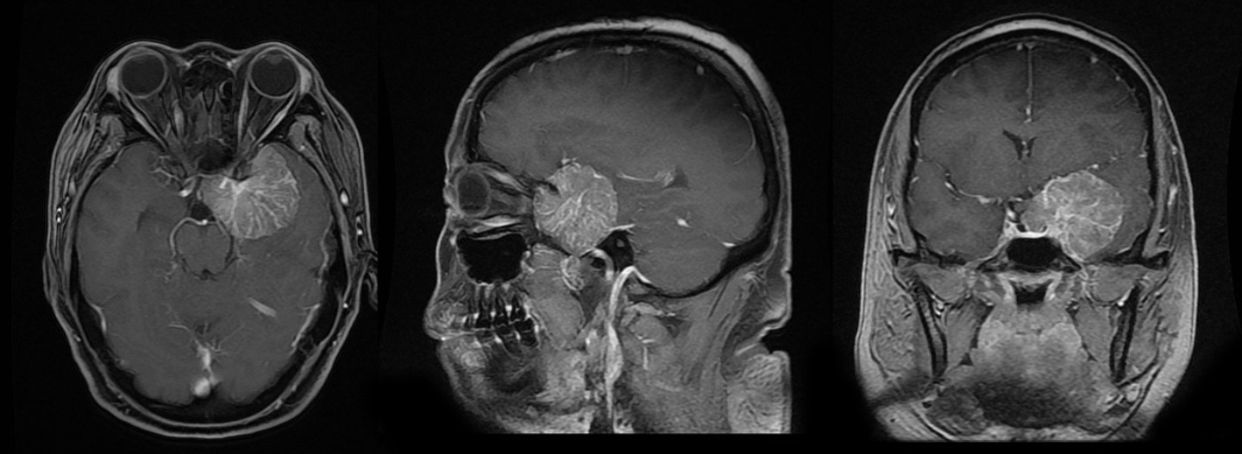

MRI检查:

CTA血管造影及三维重建:

术后MRI复查: